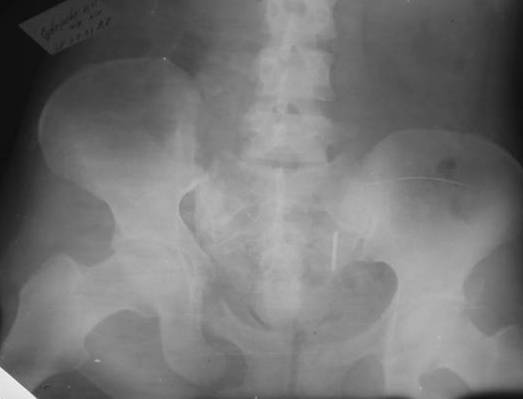

Маленькая иллюстрация (около 5 лет после травмы). Результат плохой - укорочение, хромота, периодически боли в спине, но больной отказывается от операции, видимо, не так все трагично.